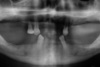

La radio panoramique d’avant traitement montre qu’il reste deux molaires au maxillaire et 8 dents à la mandibule dont 5 dents dévitalisées et deux incisives centrales légèrement mobiles . La prothèse amovible du bas ne satisfait pas non plus la patiente et la hauteur osseuse au-dessus du nerf dentaire inférieur est relativement faible des deux côtés pour poser des implants favorablement dans les secteurs postérieurs. Au maxillaire, les sini maxillaires devront être comblés pour recevoir des implants dans les secteurs postérieurs.